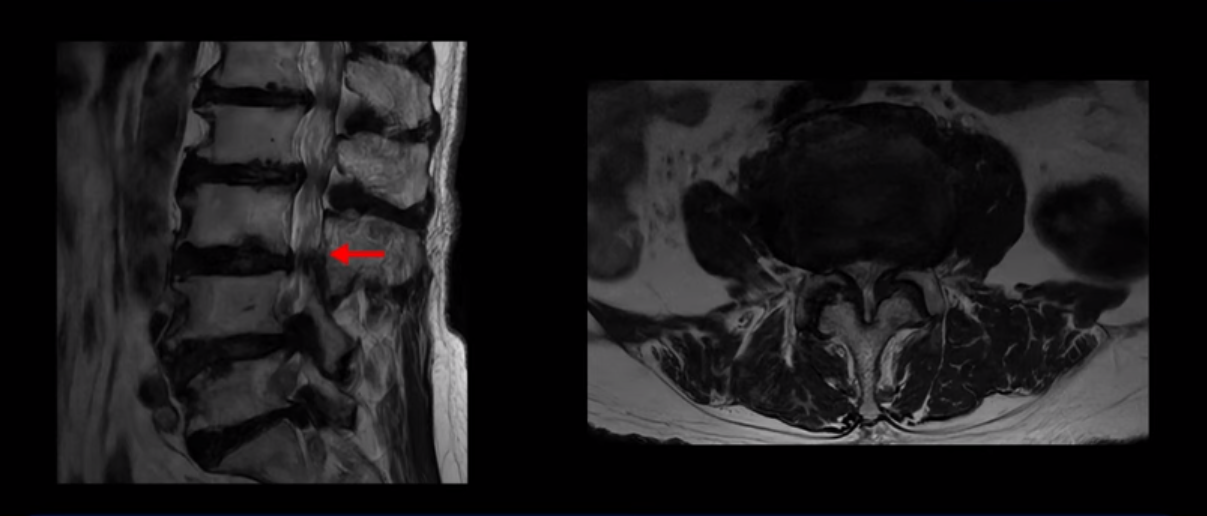

MRI 보시면 (2-8) 허리의 5마디가 전부 다 심하게 퇴행되어 있습니다.

5마디 전부 다 심한 중심성 협착이 있습니다.

이렇게 모두 다 심하게 막히는 경우는 드문데요. 또한 오른쪽, 왼쪽 신경이 빠져나가는 추간공도 다 심하게 막혀있습니다.

오른쪽, 왼쪽 이렇게 신경 구멍들이 다 좁아지고 신경이 눌리니까 양쪽 다리가 발바닥까지 아파서 걷기 어렵고 양쪽 발이 10년 넘게 시린 겁니다. 당연히 수술해서 눌린 신경을 풀어줘야 한다고 들으셨는데요. 이런 환자분을 어떻게 수술 없이 치료할까요? 지금부터 설명해 드립니다.

이분 신경이 눌리는 증상은 오래됐지만, 증상이 아주 심해진 건 올해 들어와서입니다. 그럼, 이분 MRI 영상도 이렇게 심하게 안 좋아진 게 올해 들어와서일까요? 이분의 MRI로 보이는 협착은 아주 오래된 겁니다. 그래서 신경 구멍이 심하게 좁아진 것도 올해가 아니고 오래된 겁니다. 작년, 재작년에 훨씬 덜 아팠을 때 MRI를 찍었어도 신경 구멍 좁은 정도는 별반 차이가 없었을 겁니다.

실제로 수많은 논문에서 70세 이후 MRI로 협착이 보여도 아프지 않은 무증상 협착이 많다고 설명합니다. 협착이 있어도 안 아픈 사람들이 많다는데, 이게 왜 그럴까요? 근육 기능이 정상적이고 좋은 사람들은 근육이 허리를 잘 지지해 주니까 협착이 있어도 신경이 덜 눌리거나 안 눌리는 겁니다. 즉 근육이 좋으면 신경이 덜 눌리고 근육이 좋아지면 협착증이 좋아지는 겁니다. 그래서 저희가 근육 재활치료를 통해 근육의 기능을 회복시키면서 동시에 신경의 기능을 회복시키는 치료를 하는 겁니다. 이런 분들이 근육 재활치료를 통해서 협착증 증상이 좋아진다면 이런 분들의 협착증도 아프지 않은 무증상 협착으로 바뀌게 되는 겁니다.